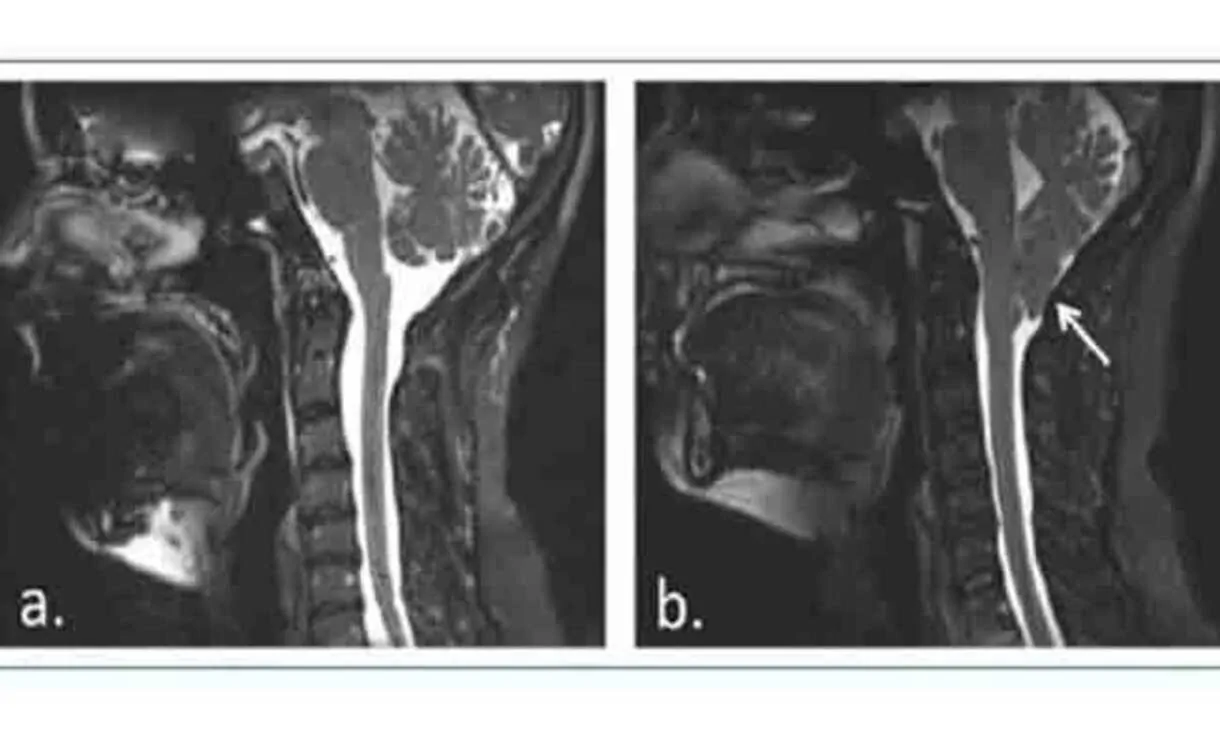

И действительно существуют методы, такие как функциональная магнитно-резонансная томография или имплантация внутричерепных электродов, которые позволяют получить информацию о мозговой активности…, но настоящая проблема лежит на молекулярном уровне: возможность анализировать развитие и межклеточные взаимодействия в процессе их возникновения, поскольку до сих пор возможности в основном сводятся к посмертным исследованиям или клеточным культурам, результаты которых во многих случаях нельзя экстраполировать на поведение человеческого мозга в целом. Чтобы решить эту проблему, одним из лучших вариантов являются мозговые органоиды.